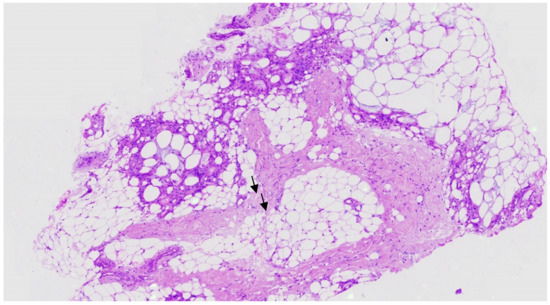

- Muzy, G.; Mayor, S.A.S.; Lellis, R.F. Subcutaneous fat necrosis of the newborn: Clinical and histopathological correlation. An. Bras. Dermatol. 2018, 93, 412–414. [Google Scholar] [CrossRef]